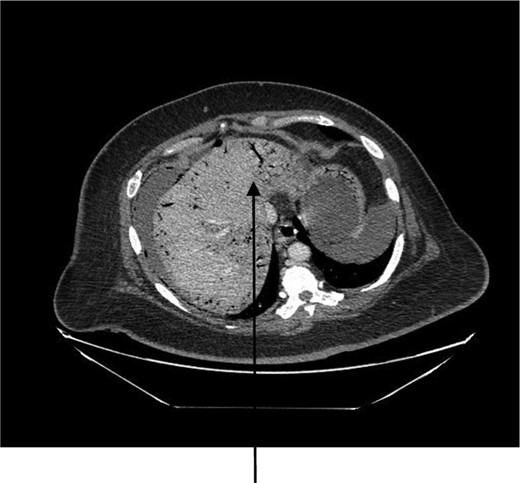

A 44-year-old female presented to the emergency department with generalized abdominal pain that became suddenly severe and diffuse 5 hours before presentation. She described the pain as sharp, alleviated by lying still on her back and worsened by moving. Pain radiated to her back. She also had watery non-bloody diarrhea that started 2 weeks before presentation. She had a medical history of poorly controlled type 1 diabetic mellitus and hypertension. No history of STDs or IUD use. Some of her labs on presentation were as follows: WBC 7.400/mm3, hemoglobin 15.6 g/dl and blood glucose 249 mg/dl. On examination, we found a hypotensive, dehydrated, obese female in septic shock with a tense, massively distended abdomen, which was diffusely tender. CT of the abdomen and the pelvis revealed pneumoperitoneum, a large right abdomino-pelvic mass measuring 17.6 × 12.1 × 20 cm, that appeared to be a septic ovarian cyst (Fig. 1) and diffuse portal venous gas throughout the liver (Fig. 2). Resuscitation and rehydration were initiated, and broad-spectrum intravenous antibiotics were administered. Hemodynamic instability continued, and she was emergently taken to the operating room for an exploratory laparotomy. Upon opening the abdomen pneumoperitoneum and diffuse purulent peritonitis was obvious. There was bullous emphysema of the wall of the uterus. The gallbladder had been previously removed. The stomach, duodenum, small bowel, appendix and colon were normal and involved only by serositis from the purulent peritonitis. A pus-filled right ovarian cyst, subscapular gas bubbles over the liver and a cecal bascule were the dominant abnormalities. A right salpingo-oophorectomy, appendectomy and peritoneal lavage with 15 liters saline and antibiotics were accomplished. She received a total of 7 liters of intravenous crystalloid resuscitation intraoperatively and 2 units of packed red cell transfusion. The patient was transferred to the surgical intensive care unit (SICU) after the procedure to continue resuscitation and critical care therapy for ongoing septic shock. The patient made a complete recovery and was discharged after a total of 11 days in SICU and 23 days in the hospital ward.

Our patient presented with HPVG, which is rare (and possibly not previously reported) complication of TOA. Hepatic portal venous gas is attributed to gas-forming organisms resulting from intra-abdominal conditions such as intestinal mucosal damage or ischemia and infection in other tissues, which may be secondary to mesenteric ischemia, ulcerative colitis perforated peptic ulcer disease, gangrenous cholecystitis and ascending cholangitis; such injuries provide a portal for intraluminal gas to enter the portal venous system [5]. Our patient had no mucosal damage or evident intestinal or other gastrointestinal pathology but had diffuse peritonitis, which could have resulted in the persorption of bacteria into the mesenteric portal circulation. About 6% of HPVG patients in one report had an intra-abdominal abscess similar to what occurred in our patient [6].